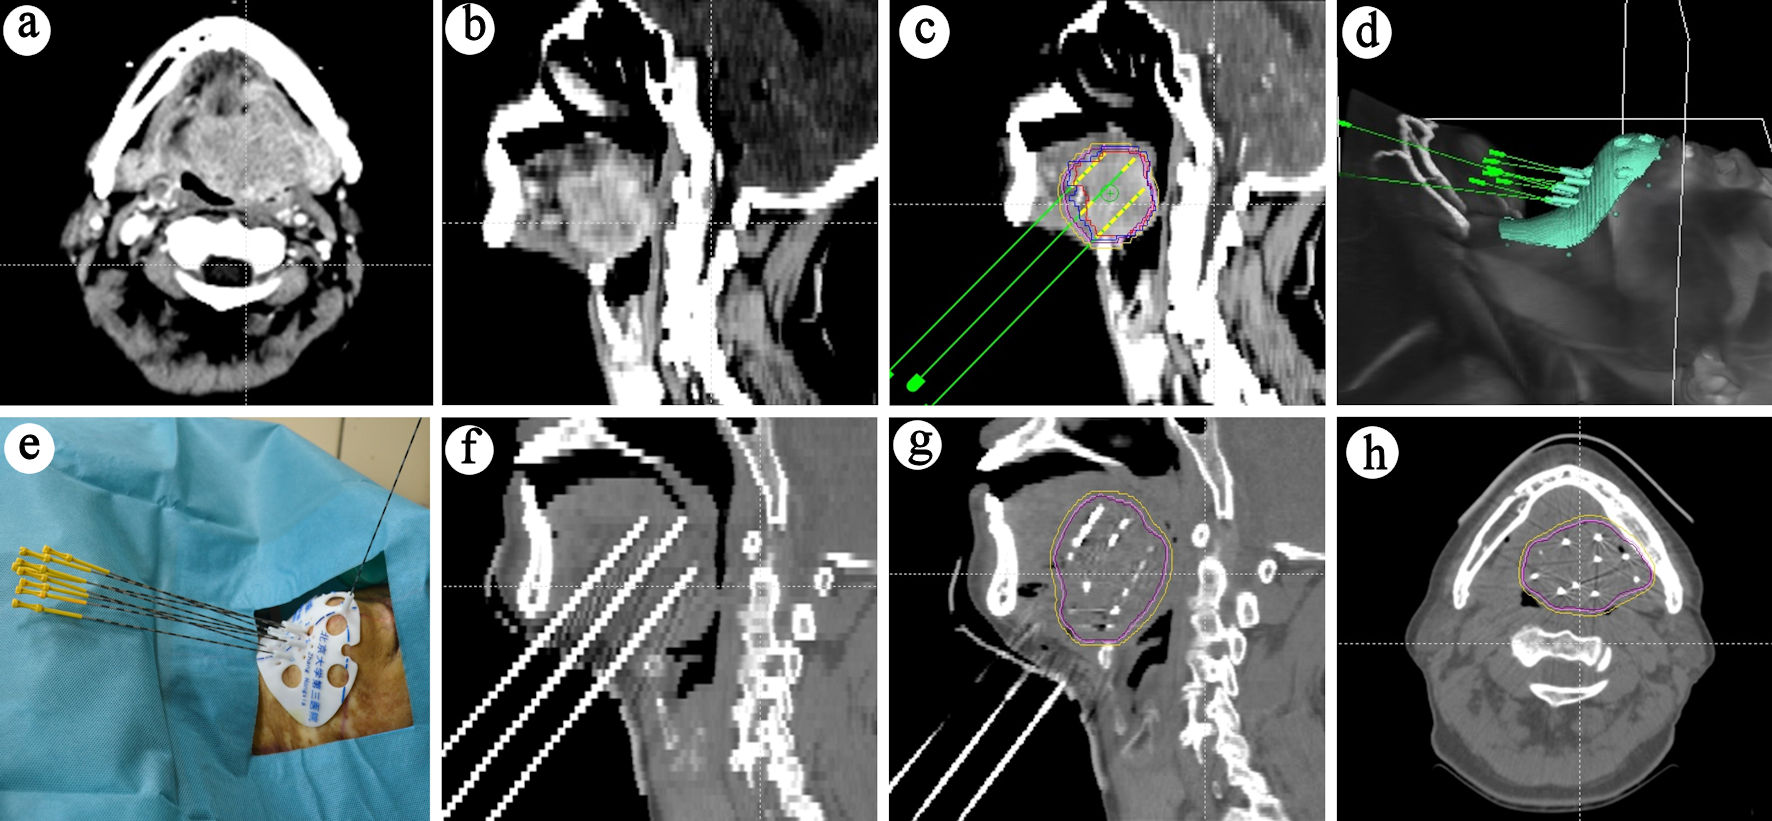

Postoperative validation included: 1) After the implantation of the seeds was completed, the seed needles were removed, and the surgical area was cleaned and bandaged with pressure gauze; 2) Post-implant CT images were transmitted to the BTPS for dose verification. The actual doses delivered to the GTV were evaluated. This technical process is illustrated in Figure 1.

![]() Click for large image | Figure 1. Treatment process schematic. (a) Cross-sectional view of the lesion. (b) Sagittal view of the lesion. (c) Preoperative planning. (d) 3D-printed template design. (e) Needle placement guided by the template. (f) CT scan post-needle placement. (g) CT scan post-seed placement. (h) Cross-sectional CT view showing seed distribution. 3D: three-dimensional; CT: computed tomography. |